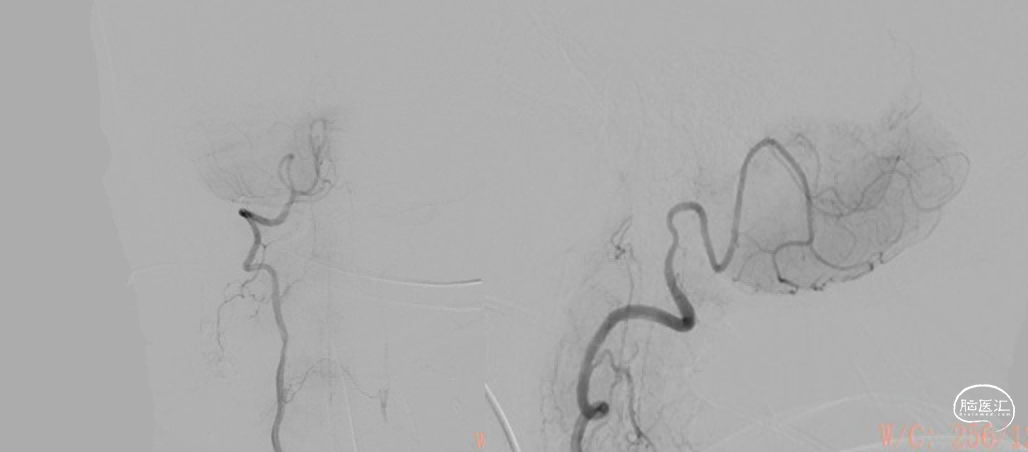

图5. 术前左椎正位:左椎起始部闭塞

图6. 右侧椎动脉正位造影:右椎V4段发育不良

综合术前辅助检查,(Core+pen)/Core=3.58;Pen>15ml;Core<70ml(图3);发病时间小于24小时,存在取栓指征,但是当地医院手术经验告诉我们左侧椎动脉慢性闭塞,且开通异常困难,常规手术方案很难成行,术前制定合理且可行的手术方案至关重要。方案1:仍采用左侧椎动脉+基底动脉取栓的正向开通方案,可能会继续浪费大量时间,甚至最后以失败告终。方案2:采用右侧椎动脉入路,由于右侧椎动脉V4段发育不良,当地医院已尝试过超选,证实无法通过V4段至基底动脉建立取栓通路。方案3:既往有文献报道开颅椎动脉直视下穿刺取栓,虽然方案可行,但我院无类似手术经验,贸然尝试风险难以把控。方案4:回顾当地医院取栓影像资料,发现双侧颈内动脉后交通呈胚胎型,是否可能通过后交通跨循环逆向超选至基底动脉取栓。患者平卧DSA床,全麻插管成功后,用碘伏常规消毒手术区皮肤,铺无菌巾单。取双侧股动脉为穿刺点,于14时00分seldinger法穿刺成功后分别置入8F穿刺鞘和5F 短鞘。行全脑血管造影显示左侧椎动脉起始部闭塞,颈升动脉通过肌支代偿V2及以远的椎动脉血流,右侧椎动脉V4段发育不良,单纯供应右侧PICA,双侧后交通动脉胚胎型。(图9,图10)首先我们仍尝试传统入路进行超选左侧椎动脉,发现左侧椎动脉开口闭塞,斑块质地坚硬,微导丝微导管无法通过。短暂尝试无果后,迅速改为右侧椎动脉入路,发现将微导丝塑型成“J”型或成袢,均无法到达右侧椎动脉V4段,遂果断决定采用跨循环取栓方案。将5F VERT造影导管超选至左侧锁骨下动脉,进行正向血流监测。6F 90cm长鞘(cook)及5F 125cm Navien导管在泥鳅导丝带领下超选进入右侧颈内动脉岩骨段。随后将Rebar18微导管在Synchro2微导丝带领下超选至大脑中动脉,并将Navien带领至右侧颈内动脉交通段。微导丝微导管回撤至颈内动脉,路图下Synchro2微导丝带领Rebar18逐步通过右侧后交通动脉,再在透视下经右侧大脑后动脉P1段盲超选至基底动脉下段。(图11-13)手推造影确认Rebar18微导管已突破血栓段,并在基底动脉真腔内。(图14)经Rebar18释放一枚solitaire FR支架(4mm×20mm)覆盖血栓段。SWIM技术负压下抽拉支架1次,抽拉过程中时刻注意系统张力,逐步回撤支架同时适度回撤Navien释放张力,以保证Navien贴近后交通开口而不向后交通动脉内继续深入。撤出支架后,Navien原位保持负压约30秒。(图15)造影复查见基底动脉及其分支再通,支架取出少量血栓(图18)。于14时45分达到远端血流mTICI3级,10分钟后复查造影显示血管通畅,于14时55分末次造影见远端血流维持mTICI3级。(图16,17)术中Dynamic CT未见明显术区出血(图19)。遂缝合穿刺点,结束手术。手术顺利,术中病人情况稳定。术末血压115/58mmHg,脉搏70次/分,呼吸12次/分,氧饱和度100%。术毕送重症监护室。图9. 双侧椎动脉造影:左侧椎动脉起始部闭塞,左侧颈升动脉肌支和右侧椎动脉通过脊髓支代偿V2及以远的椎动脉血流;右侧椎动脉V4段发育不良,单纯供应右侧PICA